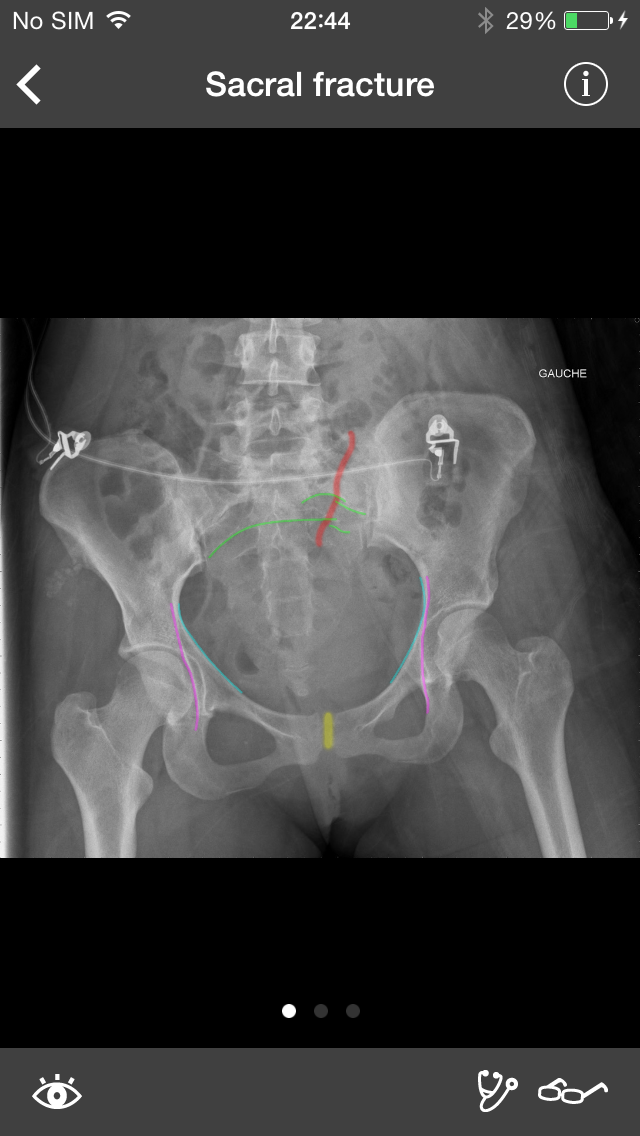

Скриншоты